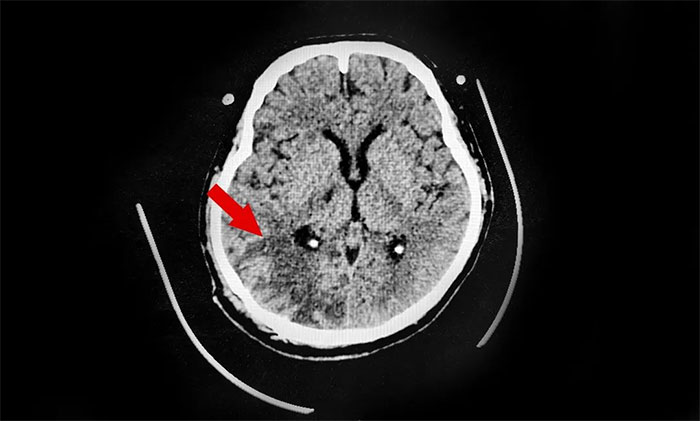

31岁的小王就是这样的年轻脑出血患者,入院诊断:脑出血、肺部感染、尿路感染、肝功能不全、低纤维蛋白原血症。神志浅昏迷状态,肢体活动障碍。家人介绍,小王工作繁忙,生活不规律,体重超标,并且还是一杆“老烟枪”,几乎每天一包烟,两个月前突发脑出血倒下。

▲ 右侧枕顶叶出血